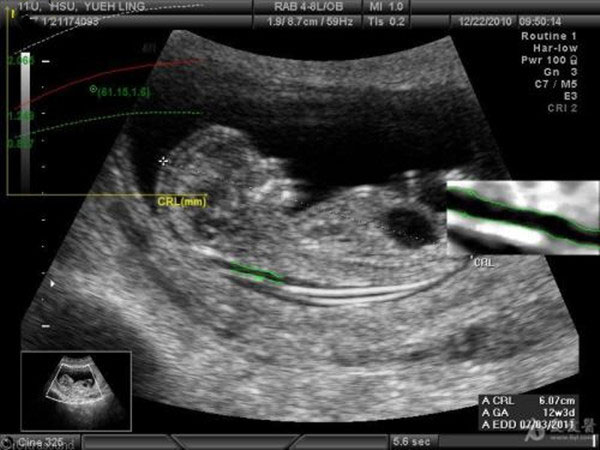

nt检查,是在怀孕11周~13周6天之前做的产检项目。若是患唐氏症的胎儿会有皮下积水的情况出现,此颈部后面的皮肤会比较厚。

nt检查数值超过3mm,则需要做进一步的检查确诊。临床上有很多一开始nt增厚,后面又被慢慢吸收的案例。当然,也有极少数不会被吸收,尤其是增厚比较大的情况。

胎儿颈项透明层,简称NT,指胎儿颈后部皮下组织内液体积聚的厚度。nt检查值小于2.5mm时判断为正常;凡测值大于等于2.5mm时诊断为颈项透明层增厚。nt增厚的原因,主要有以下这几个: